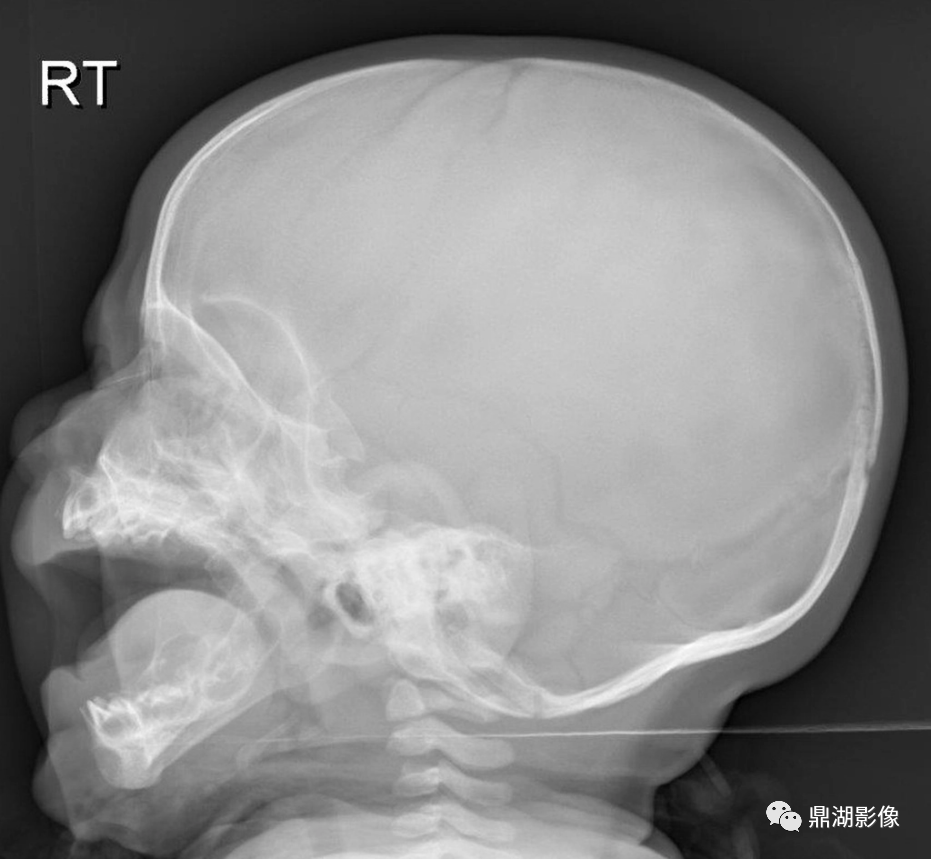

正常颅骨X光片1.头颅大小与形状头颅大小与形状做一般观察即可,如生长发育时期,头颅大小变化较大,形状...